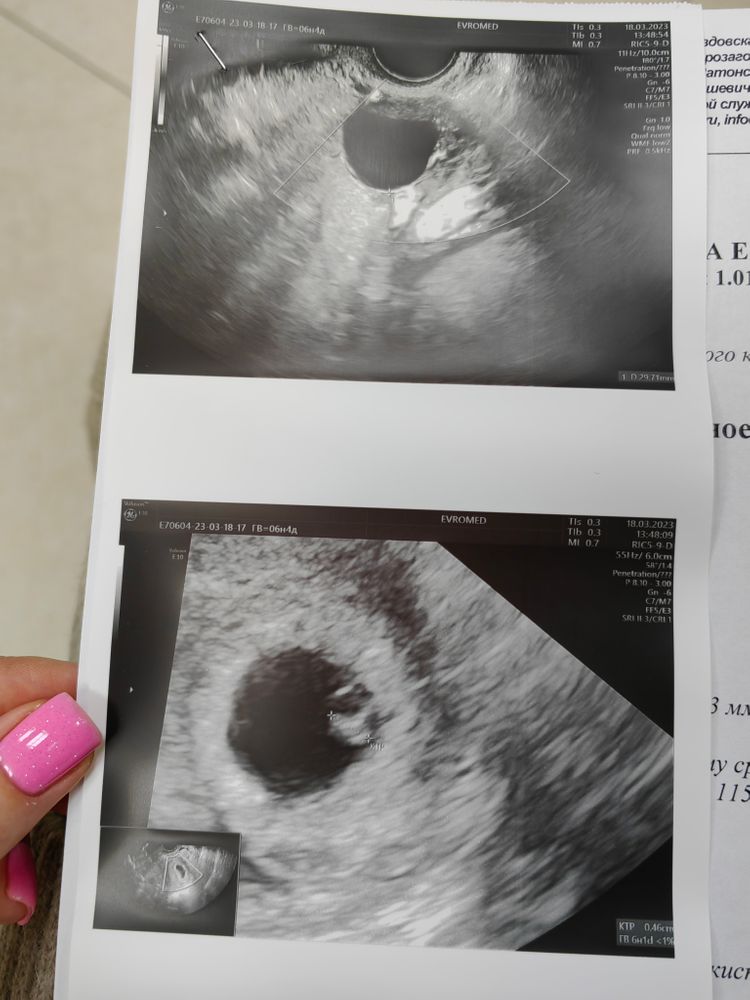

6+4, наше первое узи

УЗИ, КТГ, доплерСходила сегодня на узи, нервничала ужасно. Думаю каждая поймёт, кто пережил ЗБ 🥲

Овуля была на 19 дц, так что развиваемся ровно в срок 🥰

Сначала подумала что разбег очень сильный, тк у меня в 6+5 ктр был 8мм. А потом увидела что в заключении 6нед поставили..тогда понятно стало)

Karmilla, ну даже если срок день в день, даже по овуляцие, то ктр всё равно может быть разным) по всем табличкам есть минимальные и максимальные значения, как с хгч) врач сказала, что всё отлично, соответствует сроку, я ей сразу сказала, что овуля была на 19 дц, у вас возможно овуляция была пораньше, поэтому вы побольше)